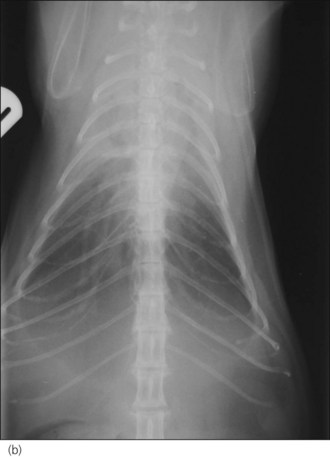

In the author’s experience, neoplasia and congestive heart failure (see Ch. 31) are the two most common causes identified in cats (see Figures 32.1-32.4).

image

Figure 32.1 Right lateral thoracic radiograph of a cat with pleural effusion secondary to a cranial mediastinal mass.